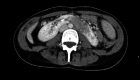

Figure 1

Figure 1. Abdominal CT scan without contrast shows horseshoe-shaped kidneys with suspicion of renal mass.